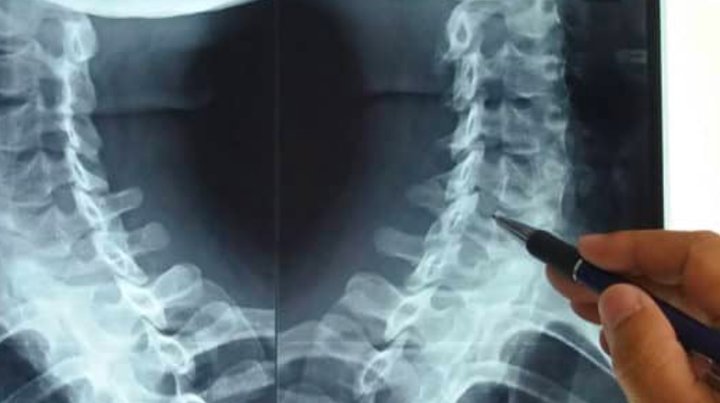

(Ảnh minh họa)